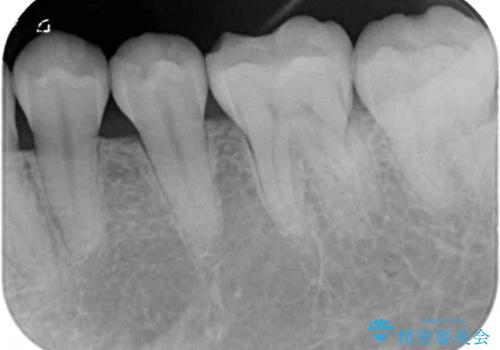

- 左下の奥歯が、冷たいものを食べるとしみて、舌で触るとザラザラすることが気になり来院された患者様です。

以前他院で治療したCR(樹脂の材料)が劣化し、その隙間から冷たいものがしみている可能性が高いことがわかりました。

嚙み合わせの力が強いため、再びCRやセラミックインレーによる修復を行っても割れてしまう可能性が高いので、

ゴールドインレーによる修復を行うこととしました。